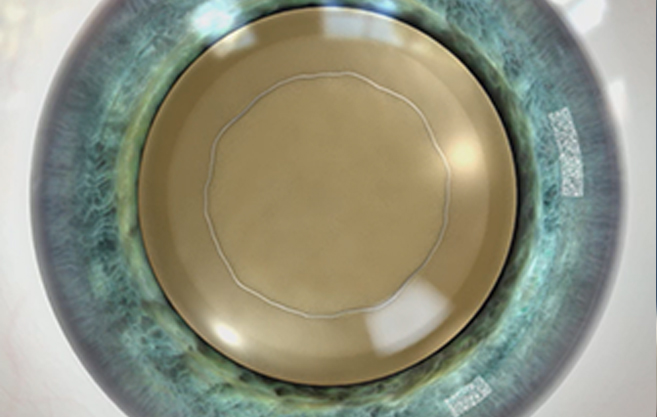

수정체낭 절개

수정체 전낭 절개시 완벽한 원이

완벽한 시력 결과를 낳습니다.

올레이저 노안백내장

정확하고 매끄러운

레이저 절개